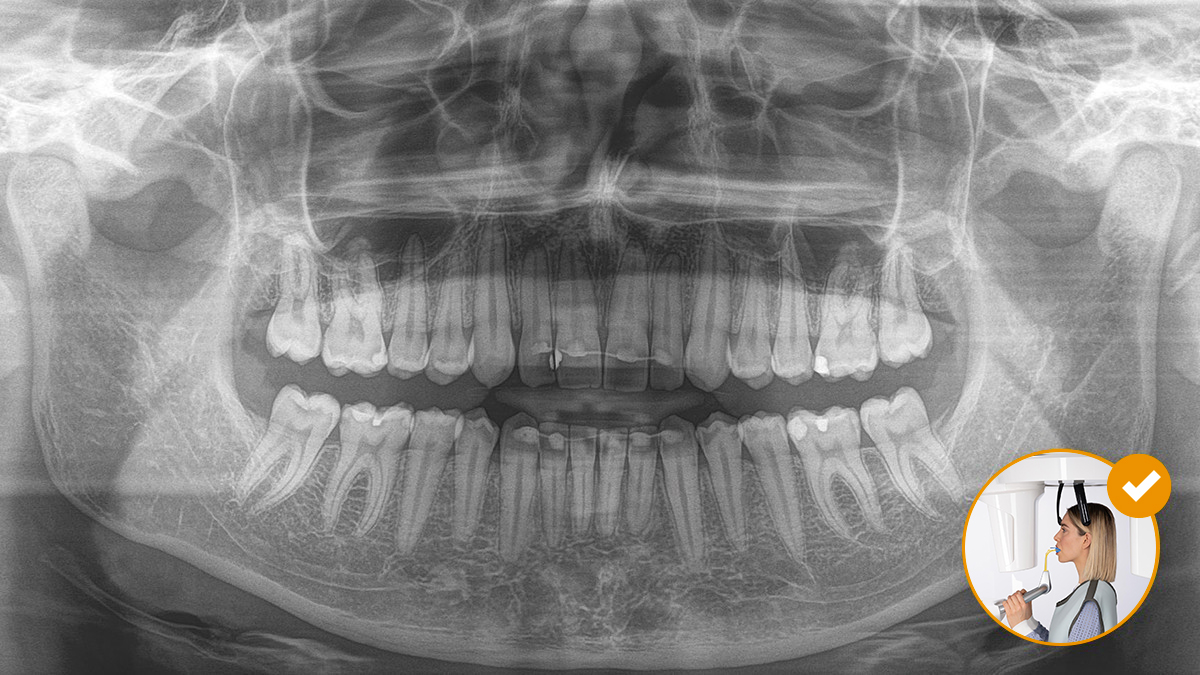

El posicionamiento correcto del paciente permite obtener imágenes de alta calidad que respaldan un diagnóstico preciso y facilitan y mejoran la experiencia del paciente.

Este es nuestro concepto de 10 puntos para facilitar el posicionamiento del paciente y la obtención de imágenes radiológicas. Se trata principalmente de dos cosas: alta calidad de imagen y comodidad para el paciente y el asistente.

Configuración intuitiva a través del EasyPad

El uso del bloque de mordida oclusal no podría ser más sencillo. Con la ayuda de los símbolos y colores en la pantalla del equipo de radiología, los profesionales disponen de toda la información necesaria para un ajuste óptimo del equipo. Las flechas iluminadas indican en qué dirección se debe mover la unidad para lograr la inclinación ideal de la cabeza. El equipo se detiene automáticamente una vez que se alcance la posición correcta.

El resultado: Escaneos precisos gracias al bloque de mordida oclusal